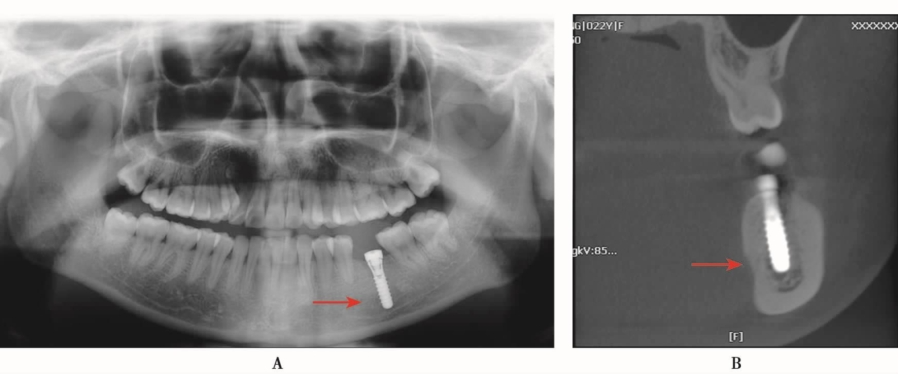

种植体进入上颌窦(图1)并不是很常见的现象,往往是由于术者对于解剖结构的理解不深或者经验不足而发生。

图1 CBCT显示种植体位于上颌窦内A.矢状位;B.水平位

种植体进入上颌窦以后,其位置和方向可以完全不一样,三维重建图像可清楚显示种植体的形状与邻近结构的相关关系(图2、图3)。

术前拍摄CBCT了解上颌骨骨质的密度是非常重要的,因为上颌骨的骨质密度一般情况下较下颌骨疏松;另外CBCT还可以了解骨质的高度与宽度、上颌窦内的状况及邻近牙齿等的相关信息,避免发生此类意外。